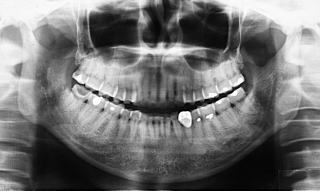

当Clinicでは、すべてInterdisciplinary Treatment(包括的治療)を基本にしている。患者は38年間当Clinicで口腔管理をしている症例

である。開業当初から当診療システムで38年間口腔管理をしている。Panorama、CTなどレントゲンを介しての顎骨・歯槽骨の形態・骨

量などを観察したもので、歯槽骨の吸収状態から診ても、ほぼ二十歳代に相当するように思われる。過去の論文を見ても、口腔内写真

患者:83歳、女性

医療面接:子宮癌(全摘)、卵巣全摘、狭心症(1997年)、白内障手術(RL)(2009年)。帯状疱疹(体幹部、肋間神経支配部)(2010年)は当Clinicで治療。M.K.(胃癌)部分(1/2)開腹手術(2014年)。M.K.手術前の周術前口腔ケアでは、大学病院口腔外科受診時、担当医が口腔状態の良好状態に驚愕されたようだ。現在も毎月のS.P.T.(Supportive

Periodontal Therapy)を継続中。

(図15)2015年7月27日、83歳。高年齢と残存歯数ばかりが問題視されているが、歯槽骨の状態、歯肉、Pocketの状態を含めた歯周病を評価すべきである

歯周病治療38年経過:83歳(女性)残存歯数28本